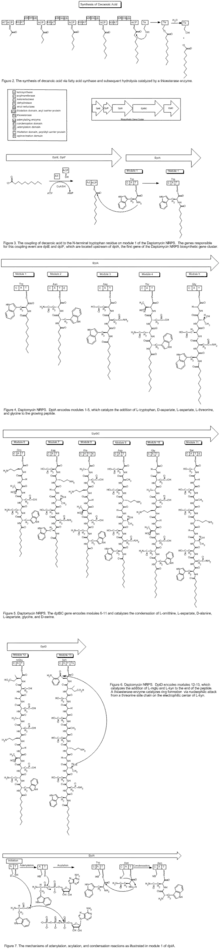

Daptomycin is a cyclic lipopeptide antibiotic produced by Streptomyces roseosporus.[30][31] Daptomycin consists of 13 amino acids, 10 of which are arranged in a cyclic fashion, and three on an exocyclic tail. Two nonproteinogenic amino acids exist in the drug, the unusual amino acid L-kynurenine (Kyn), only known to daptomycin, and L-3-methylglutamic acid (mGlu). The N-terminus of the exocyclic tryptophan residue is coupled to decanoic acid, a medium-chain (C10) fatty acid. Biosynthesis is initiated by the coupling of decanoic acid to the N-terminal tryptophan, followed by the coupling of the remaining amino acids by nonribosomal peptide synthetase (NRPS) mechanisms. Finally, a cyclization event occurs, which is catalyzed by a thioesterase enzyme, and subsequent release of the lipopeptide is granted.

The NRPS responsible for the synthesis of daptomycin is encoded by three overlapping genes, dptA, dptBC and dptD. The dptE and dptF genes, immediately upstream of dptA, are likely to be involved in the initiation of daptomycin biosynthesis by coupling decanoic acid to the N-terminal Trp.[32] These novel genes (dptE, dptF ) correspond to products that most likely work in conjunction with a unique condensation domain to acylate the first amino acid (tryptophan). These and other novel genes (dptI, dptJ) are believed to be involved in supplying the nonproteinogenic amino acids L-3-methylglutamic acid and Kyn; they are located next to the NRPS genes.[32]

The decanoic acid portion of daptomycin is synthesized by fatty acid synthase machinery (Figure 2). Post-translational modification of the apo-acyl carrier protein (ACP, thiolation, or T domain) by a phosphopantetheinyltransferase (PPTase) enzyme catalyzes the transfer of a flexible phosphopantetheine arm from coenzyme A to a conserved serine in the ACP domain through a phosphodiester linkage. The holo-ACP can provide a thiol on which the substrate and acyl chains are covalently bound during chain elongations. The two core catalytic domains are an acyltransferase (AT) and a ketosynthase (KS). The AT acts upon a malonyl-CoA substrate and transfers an acyl group to the thiol of the ACP domain. This net transthiolation is an energy-neutral step. Next, the acyl-S-ACP gets transthiolated to a conserved cysteine on the KS; the KS decarboxylates the downstream malonyl-S-ACP and forms a β-ketoacyl-S-ACP. This serves as the substrate for the next cycle of elongation. Before the next cycle begins, however, the β-keto group undergoes reduction to the corresponding alcohol catalyzed by a ketoreductase domain, followed by dehydration to the olefin catalyzed by a dehydratase domain, and finally reduction to the methylene catalyzed by an enoylreductase domain. Each KS catalytic cycle results in the net addition of two carbons. After three more iterations of elongation, a thioesterase enzyme catalyzes the hydrolysis, and thus release, of the free C-10 fatty acid.

To synthesize the peptide portion of daptomycin, the mechanism of an NRPS is employed. The biosynthetic machinery of an NRPS system is composed of multimodular enzymatic assembly lines that contain one module for each amino acid monomer incorporated.[33] Within each module are catalytic domains that carry out the elongation of the growing peptidyl chain. The growing peptide is covalently tethered to a thiolation domain; here it is termed the peptidyl carrier protein, as it carries the growing peptide from one catalytic domain to the next. Again, the apo-T domain must be primed to the holo-T domain by a PPTase, attaching a flexible phosphopantetheine arm to a conserved serine residue. An adenylation domain selects the amino acid monomer to be incorporated and activates the carboxylate with ATP to make the aminoacyl-AMP. Next, the A domain installs an aminoacyl group on the thiolate of the adjacent T domain. The condensation (C) domain catalyzes the peptide bond forming reaction, which elicits chain elongation. It joins an upstream peptidyl-S-T to the downstream aminoacyl-S-T (Figure 7). Chain elongation by one aminoacyl residue and chain translocation to the next T domain occurs in concert. The order of these domains is C-A-T. In some instances, an epimerization domain is necessary in those modules where L-amino acid monomers are to be incorporated and epimerized to D-amino acids. The domain organization in such modules is C-A-T-E.[33]

The first module has a three-domain C-A-T organization; these often occur in assembly lines that make N-acylated peptides.[33] The first C domain catalyzes N-acylation of the initiating amino acid (tryptophan) while it is installed on T. An adenylating enzyme (Ad) catalyzes the condensation of decanoic acid and the N-terminal tryptophan, which incorporates decanoic acid into the growing peptide (Figure 3). The genes responsible for this coupling event are dptE and dptF, which are located upstream of dptA, the first gene of the Daptomycin NRPS biosynthetic gene cluster. Once the coupling of decanoic acid to the N-terminal tryptophan residue occurs, the condensation of amino acids begins, catalyzed by the NRPS.

The first five modules of the NRPS are encoded by the dptA gene and catalyze the condensation of L-tryptophan, D-asparagine, L-aspartate, L-threonine, and glycine, respectively (Figure 4). Modules 6-11, which catalyze the condensation of L-ornithine, L-aspartate, D-alanine, L-aspartate, glycine, and D-serine are encoded for the dptBC gene (Figure 5). dptD catalyzes the incorporation of two nonproteinogenic amino acids, L-3-methylglutamic acid (mGlu) and Kyn, which is only known thus far to daptomycin, into the growing peptide (Figure 6).[31] Elongation by these NRPS modules ultimately leads to macrocyclization and release in which an α-amino group, namely threonine, acts as an internal nucleophile during cyclization to yield the 10-amino-acid ring (Figure 6). The termination module in the NRPS assembly line has a C-A-T-TE organization. The thioesterase domain catalyzes chain termination and release of the mature lipopeptide.[33]

The molecular engineering of daptomycin, the only marketed acidic lipopeptide antibiotic to date (Figure 8), has seen many advances since its inception into clinical medicine in 2003.[34] It is an attractive target for combinatorial biosynthesis for many reasons: second generation derivatives are currently in the clinic for development;[35] Streptomyces roseosporus, the producer organism of daptomycin, is amenable to genetic manipulation;[36] the daptomycin biosynthetic gene cluster has been cloned, sequenced, and expressed in S. lividans;[35] the lipopeptide biosynthetic machinery has the potential to be interrupted by variations of natural precursors, as well as precursor-directed biosynthesis, gene deletion, genetic exchange, and module exchange;[36] the molecular engineering tools have been developed to facilitate the expression of the three individual NRPS genes from three different sites in the chromosome, using ermEp* for expression of two genes from ectopic loci;[37] other lipopeptide gene clusters, both related and unrelated to daptomycin, have been cloned and sequenced,[29] thus providing genes and modules to allow the generation of hybrid molecules;[36] derivatives can be afforded via chemoenzymatic synthesis;[38] and lastly, efforts in medicinal chemistry are able to further modify these products of molecular engineering.[35]

New derivatives of daptomycin (Figure 9) were originally generated by exchanging the third NRPS subunit (dptD) with the terminal subunits from the A54145 (Factor B1) or calcium-dependent antibiotic pathways to create molecules containing Trp13, Ile13, or Val13.[39] dptD is responsible for incorporating the penultimate amino acid, 3-methyl-glutamic acid (3mGlu12), and the last amino acid, Kyn13, into the chain. This exchange was achieved without engineering the interpeptide docking sites. These whole-subunit exchanges have been coupled with the deletion of the Glu12-methyltransferase gene, with module exchanges at intradomain linker sites at Ala8 and Ser11, and with variations of natural fatty-acid side chains to generate over 70 novel lipopeptides in significant quantities; most of these resultant lipopeptides have potent antibacterial activities.[29][39] Some of these compounds have in vitro antibacterial activities analogous to daptomycin. Further, one displayed ameliorated activity against an E. coli imp mutant that was defective in its ability to assemble its inherent lipopolysaccharide. A number of these compounds were produced in yields that spanned from 100 to 250 mg/liter; this, of course, opens up the possibility for successful scale-ups by fermentation techniques. Only a small percentage of the possible combinations of amino acids within the peptide core have been investigated thus far.[40]